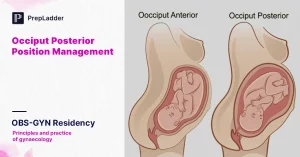

– Occiput posterior position (Inkondo y’umutwe ireba inyuma)

Mu buryo nanone busanzwe, umwana aba yicaye mu nda ku buryo umutwe we ureba imbere (occiput anterior), bityo mu maso he herekeza ku gice cy’inyuma cy’umubyeyi. Ibi bituma gusunika bigenda neza.Ariko mu Occiput Posterior Position:- Umwana aba yicaye ku buryo inyuma y’umutwe (occiput) ireba inyuma y’umubyeyi, mu gihe mu maso he herekeza imbere ku gice cy’inda y’umubyeyi.

– Ibi bivuze ko mu gihe cyo gusunika, umutwe w’umwana uticaye neza mu nkondo y’umura, bigatuma inzira iba ngufi kandi igoranye.

– Umubyeyi ashobora kugira ibise bimara igihe kirekire, akababara cyane mu gice cy’inyuma (lower back pain), kandi gusunika bikaba bigorana.